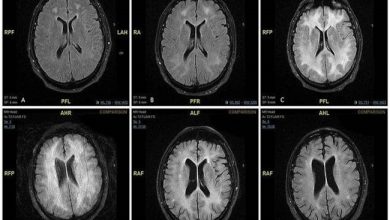

صورة شعاعية تكشف ما يفعله الكوكايين بالدماغ